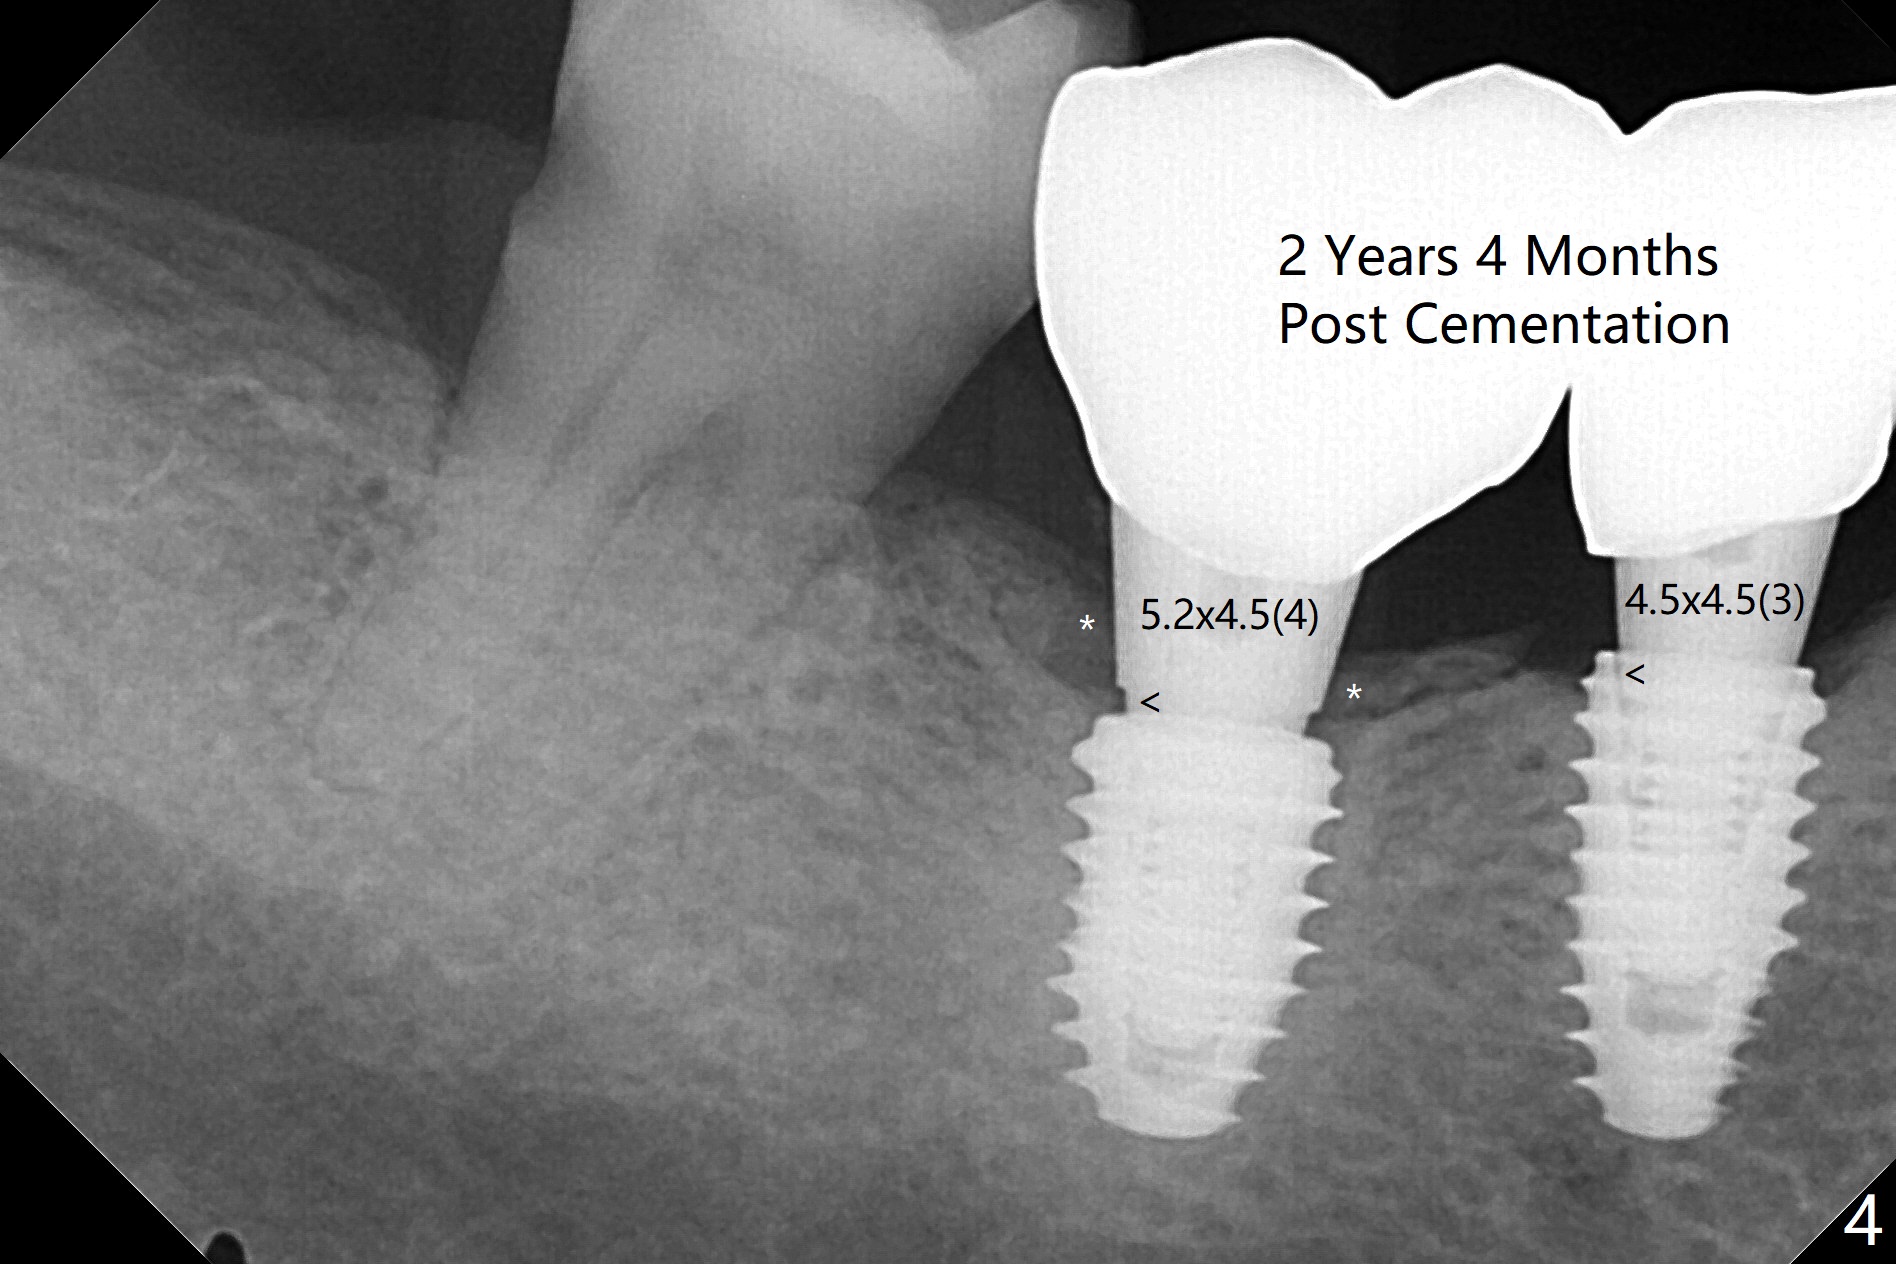

With one carpule of Xylocaine 34 mg with Epinephrine 17 mcg (infiltration) and slow osteotomy with guide, two short implants are placed at #29 and 30 painless with >45 Ncm (Fig.1). Healing abutments are placed without bony interference (Fig.2). It appears that the tooth #31 shifts mesially (Fig.2 arrow), which should be slowed down and/or corrected with early provisional. There is no bone loss 4.5 months postop (Fig.3). With placement of 4.5x4.5(3) and 5.2x4.5(4) mm abutments at #29 and 30, respectively, no limited orthodontic treatment seems to be needed. The screw at #29 becomes loose 4 months post cementation and a few days after #19 implant is loose (bruxism). In fact this is not completely true, since the abutment at #29 is incompletely seated (Fig.4). The abutment at #30 is also incompletely seated because of the vertical gap (<), probably due to mesial and distal crestal interference (*).